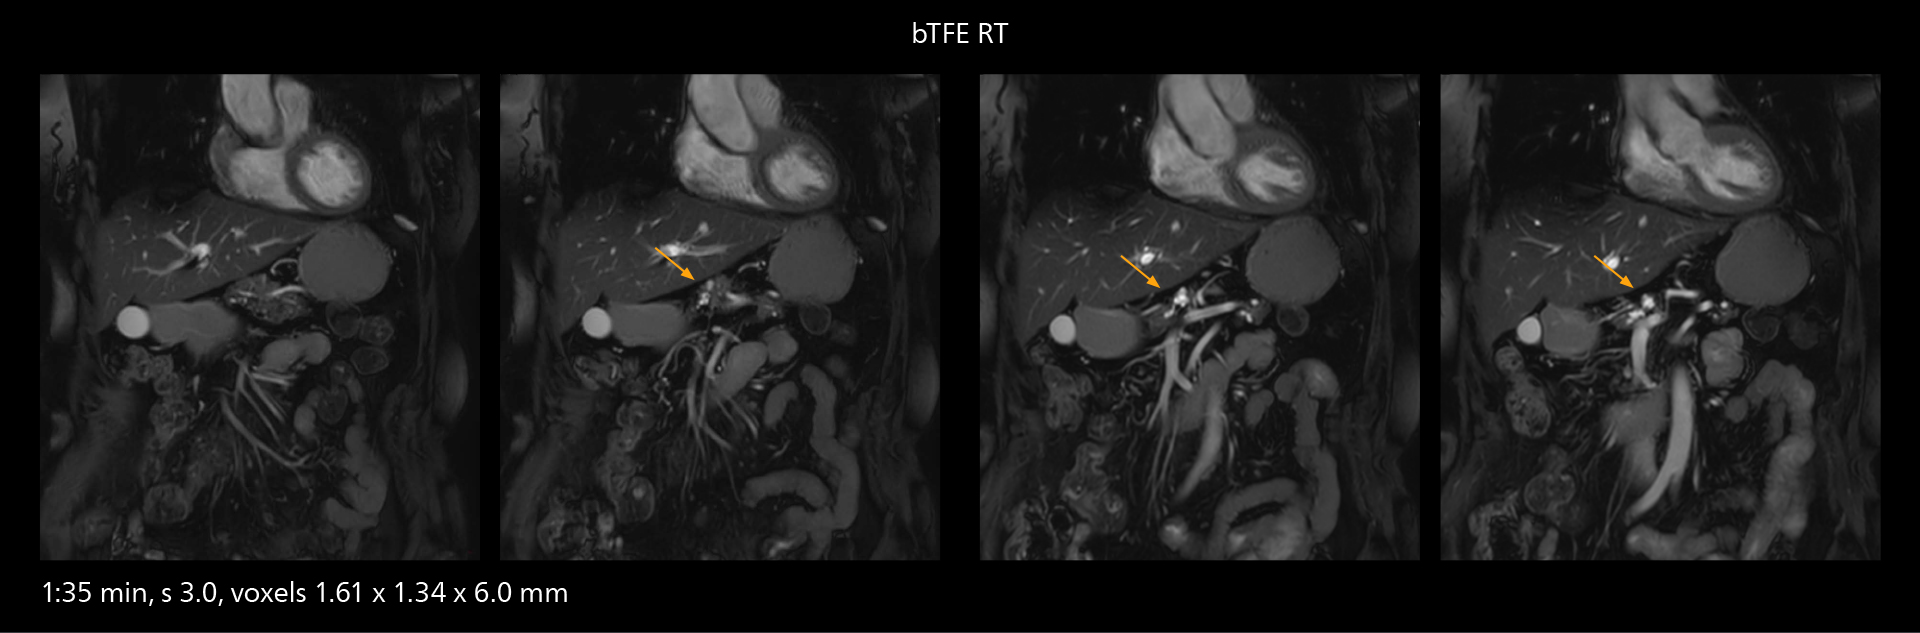

MRCP

With SmartPath to Elition X, the MRCP examinations at Sannodai Hospital benefit from VitalEye: respiratory synchronization is possible without respiratory belt positioning and image quality is excellent.